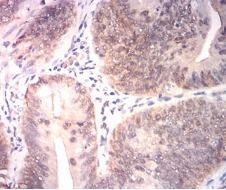

BRIP1 Mouse Monoclonal antibody[1B8F9]

Immunogen:    Purified recombinant fragment of human BRIP1 (AA: 904-986) expressed in E. Coli.

IHC    1/200 - 1/1000